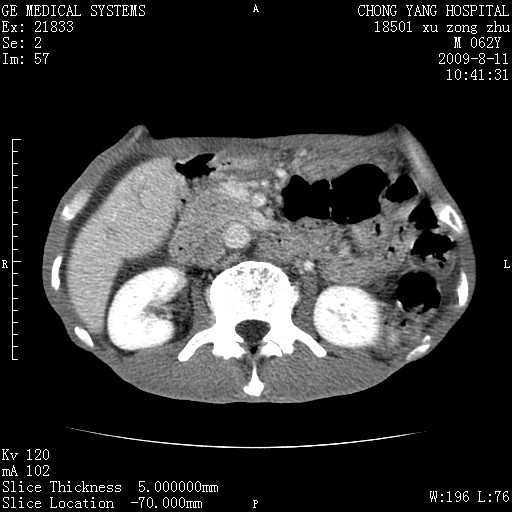

以下是引用杀毒软件在2009-8-11 16:35:00的发言:[br]肝内胆管扩张局限于左叶,胆管内有结石伴肝外胆管结石,胆管壁增厚呈弥漫性并发腹腔积液,胰腺边界模糊。[br][br]考虑---胆总管及肝内胆管结石继发胆管炎及胰腺炎,左肾下极囊肿,腹水。

以下是引用zjzjr在2009-8-11 17:35:00的发言:[br]肝内胆管扩张局限于左叶,胆管内有结石伴肝外胆管结石,胆管壁增厚呈弥漫性并发腹腔积液。[br][br]考虑---胆总管及肝内胆管结石继发胆管炎,左肾下极囊肿,腹水。